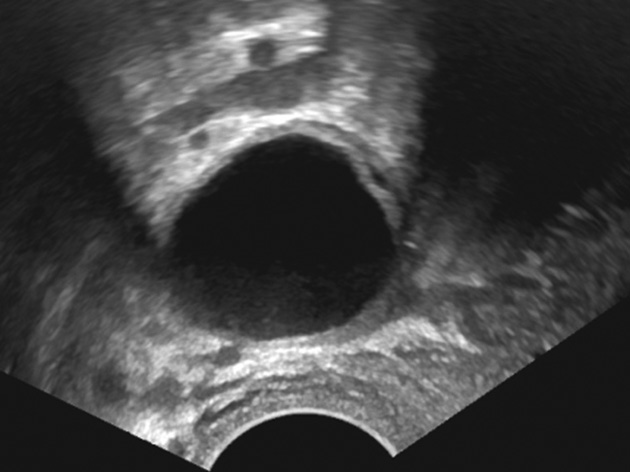

К «практически наверняка доброкачественным» относятся образования, имеющие «классическую» эхографическую картину доброкачественного образования (простая и однокамерная киста, геморрагическая киста, эндометриома, дермоидная киста и фиброма) (рис. 1–6). Понятие однокамерной кисты относительно новое и подразумевает наличие в полости кисты ≥1 неполной перегородки, локальных утолщений на стенке высотой до 3 мм, внутренних эхо в полости (рис. 2). Одиночная тонкая (≤3 мм) перегородка в полости кисты считается доброкачественной находкой [22].

Рис. 2. Однокамерная киста яичника. Киста с одиночной неполной перегородкой и внутренним эхо

Fig. 2. Uniloculated ovarian cyst: a cyst with one incomplete septum and internal echoes